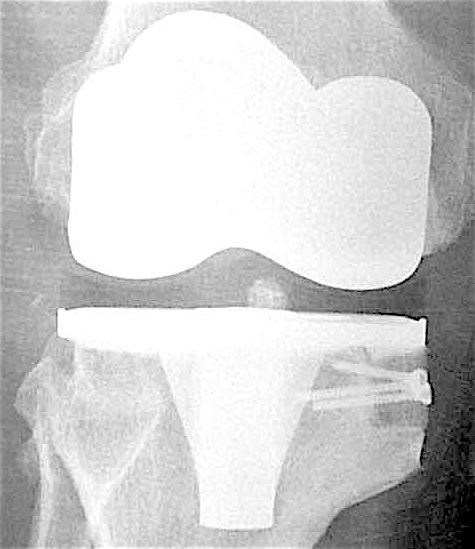

Больной З. 72 года. Диагноз: посттравматический деформириующий правосторонний гонартроз, genu valgum.

Сделано тотальное эндопротезирование коленного сустава, костная аллопластика материалом «Лиопласт».